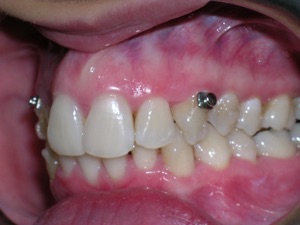

And more.

Needless to say, we were both quite happy with the outcome. Using elastics we were able to push back the back teeth and create space for the two teeth stuck behind.